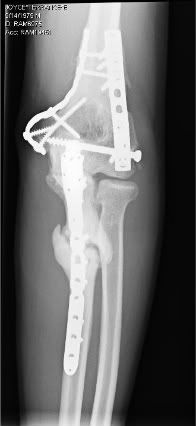

Before going under knife on July 20th, most would tease me with comparisons to Marvel's Wolverine as a result of the comical amount of surgical hardware I have holding my frame together.

Hunky superhero jokes aside, I've been living with several left ulna "non-unions" since 2005 resulting in "overactive bone growth" in my arm.

Following my recent surgery, though, I only wish I was blessed with those crazy regenerative powers he has.